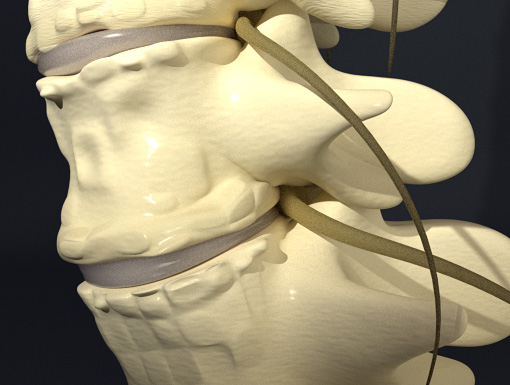

Spinal decompression gently pulls the vertebral joints apart.

It is believed this process produces a negative pressure inside the disc causing any herniated material to slowly recede back into the disc.

3D animation explains how the non-surgical spinal decompression process can relieve many back pain issues.